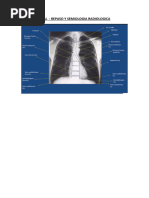

Enfermedades de Neumo en RX

Rx de Torax: